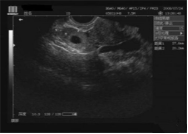

現代的婦科B超檢查有兩種方式:腹部和經陰道腔內的B超。

做腹部的B超檢查,需要膀胱充盈下才能看清楚子宮附件及盆腔的圖像,這也就是為什么醫生會關心我們多喝水,憋尿的原因。

陰式B超(陰超)是一種腔內超聲,是將超聲探頭直接放在陰道內進行超聲檢查的一種方法,而陰式B超(陰超)不需要憋尿,探頭在陰道內緊貼宮頸及后穹窿不像腹部B超,聲束要經過腹部皮膚、肌肉,所以盆腔顯示更加清晰。尤其是對后位子宮、子宮內膜癌、子宮肌瘤、前置胎盤等的觀察,圖像顯示比腹部超聲明顯清晰。(無性生活的女性朋友需提前告知醫師,此項檢查禁止操作)。